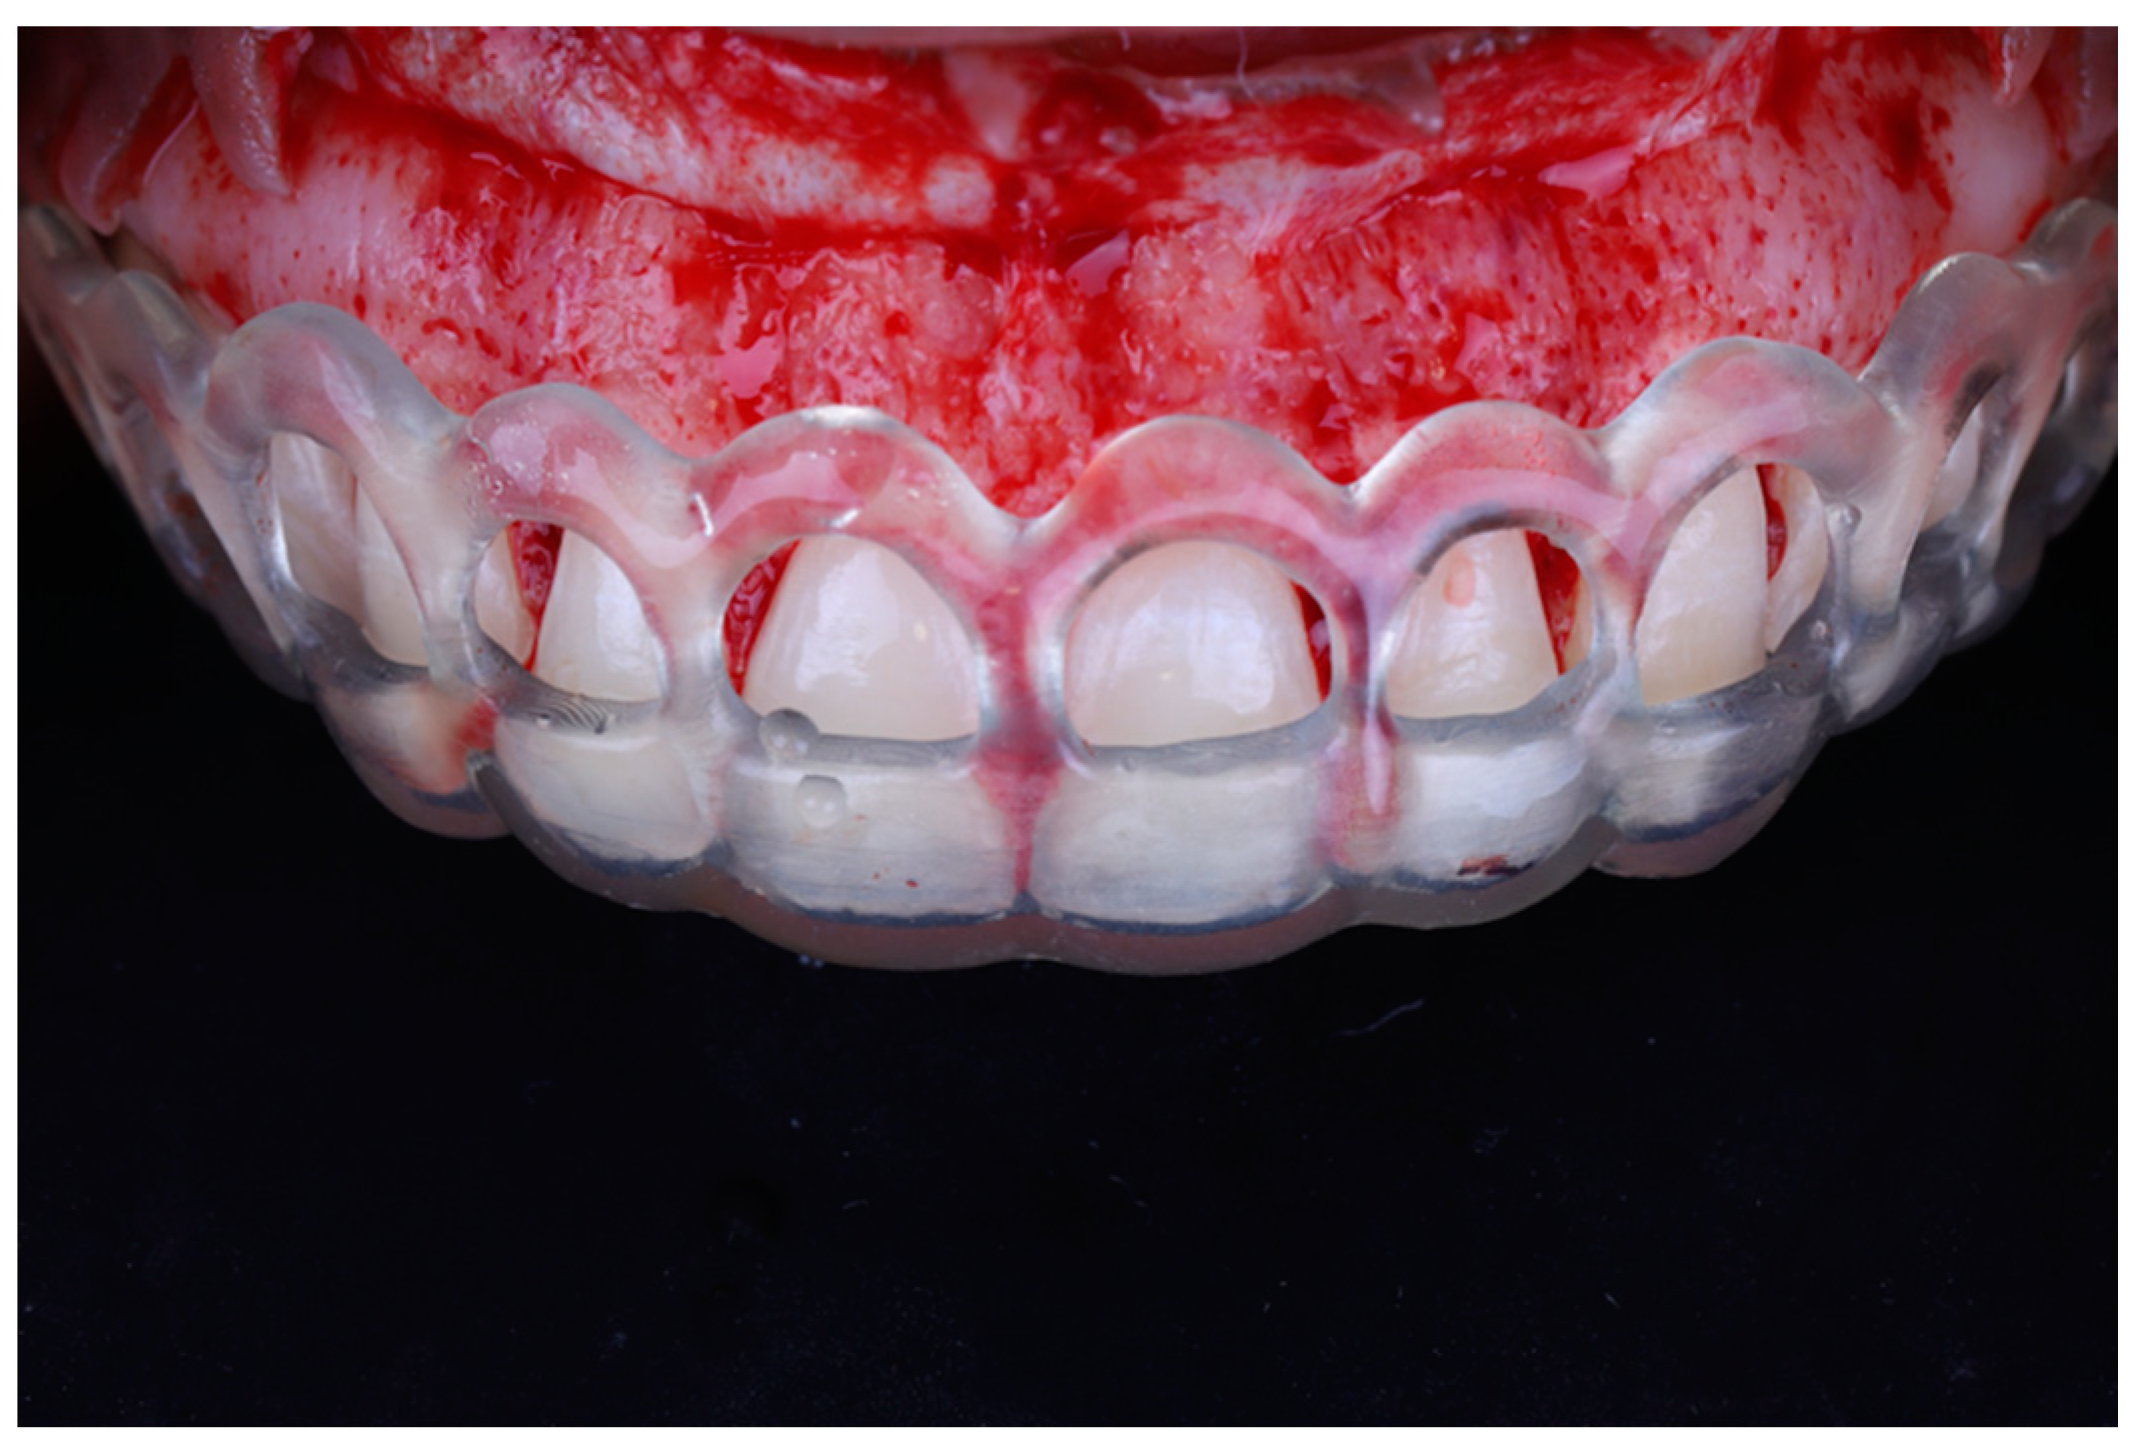

A full thickness mucoperiosteal flap was elevated past the mucogingival junction (Figure 7). The surgical guide was then placed again to determine the extent of osteoectomy needed (Figure 8), and the bone was marked with a round carbide bur. Using an end cutting carbide bur, osteoectomy was then performed; osteoplasty was performed after to remove buccal bone buttressing (Figure 9). The guide was then placed for a final check before internal vertical mattress sutures were placed using a monofilament non-resorbable material (5.0 Prolyne, Ethicon Inc, Somerville, NJ, USA) and hemostasis was ensured.

Figure 8.

Surgical guide placed to determine level of osteoectomy.